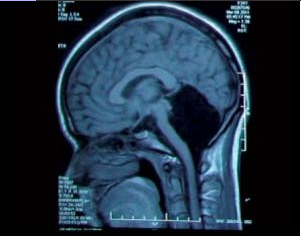

图示:上图空洞处显示小脑缺失,下图为正常脑部(供读者对比)

当医生拿到患者的CAT结果后,一眼就发现,在影像所示的脑部解剖结构中,整个小脑部分空洞。该部位无实质性组织,取而代之的是满满充盈的脑脊液。

小脑位于大脑两个半球的下方,由更小的、更紧凑的褶皱组织构成,在影像学中可看到与其它脑部组织的明显差异。小脑占据脑容量约10%的部分,但包含了50%的神经元。